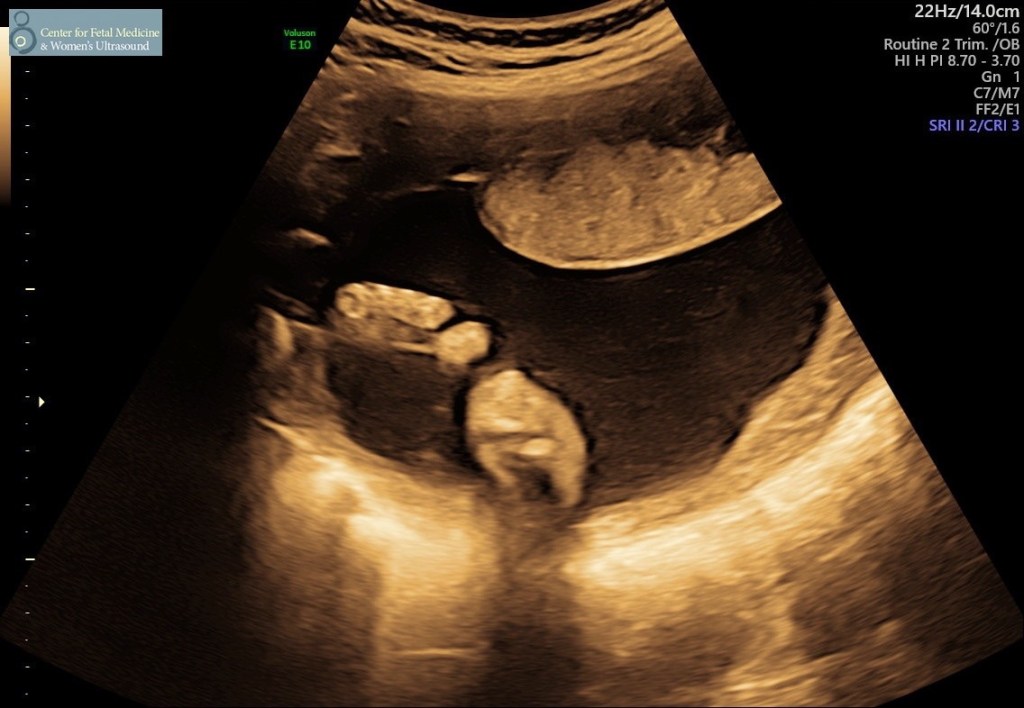

Perinatologistは女性の方でとても優しかった☺︎色々話しながらエコーをとって、色々細かく説明してくれて、これまでのサクサクエコーとは大違い。改めて、日本では「はい、〇〇ですねー。正常です。次は〇〇です。はい、いいですねー。」とワントーンなのが、こちらは”The heart looks good! Beautiful.”と患者が安心したり、ポジティブになる言葉やトーンを使ってくれるので気持ちいい。しかもここは携帯を置く台まで用意してくれるので、一部始終の動画を撮ることができた!

日本と変わらず、こんな感じです

エコーの結果、サイズや内臓も全て正常で、全く問題がないとのこと☺︎